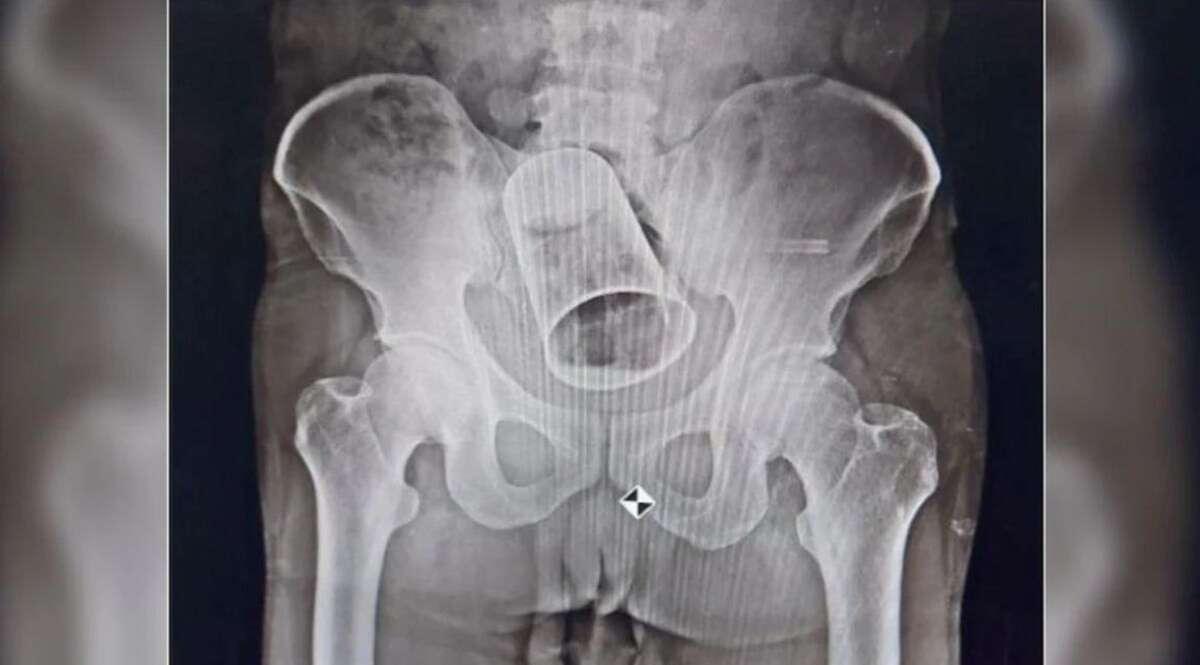

जैसे ही वह अपने घर पहुंचा तो देखा कि उसके पेट में सूजन आ गई थी. परिवार वालों को कृष्णा ने फिर सारी बात बताई और एमकेसीजी अस्पताल में चेकअप करवाया. कृष्णा की जब X-Ray रिपोर्ट आई तो पता चला उसकी आंत में स्टील का गिलास फंस गया है. डॉक्टरों ने पहले मलाशय के माध्यम से कांच निकालने की कोशिश की. लेकिन आंत के बीच गिलास इस तरह फंसा हुआ था कि उसे निकाला नहीं जा सका.

आंत काटकर गिलास निकाला बाहर

फिर डॉक्टरों ने उसे ऑपरेशन की सलाह दी. सर्जरी डिपार्टमेंट के हेड प्रोफेसर डॉक्टर चरण पांडा ने ऑपरेशन के लिए टीम बनाई. इस टीम में शामिल असिस्टेंट प्रोफेसर संजीत कुमार नायक, डॉ. सुब्रत बराल, डॉ. सत्यस्वरूप और डॉ प्रतिभा ने कृष्णा की सर्जरी की. उन्होंने बड़ी ही सावधानी से आंत को काटकर स्टील का गिलास बाहर निकाल लिया. वहीं, अस्पताल के सूत्रों ने बताया कि सर्जरी के बाद से अब कृष्णा ठीक हो रहा है. जल्द ही उसे अस्पताल से छुट्टी दे दी जाएगी.